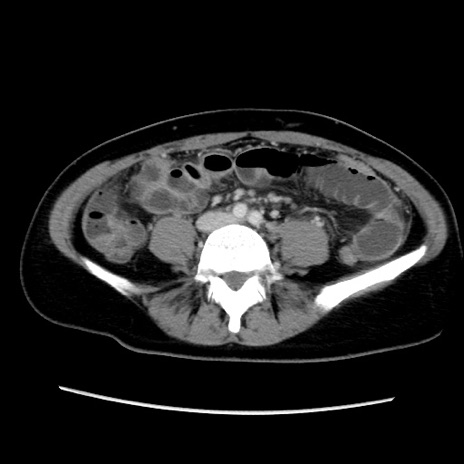

症例39(横断像)

【症例】40歳代女性

【主訴】上下腹部痛

【現病歴】2日目から下腹部痛あり。夜間は痛みで眠れなかった。昨日より上腹部痛と下痢が出現。臥位で痛みは軽快したため、休んでいた。本日になって臥位でも立位でも痛みが強くなってきたため救急要請。

【既往歴】子宮内膜症

【身体所見】部:平坦・軟、左上下腹部に圧痛あり、反跳痛あり。

【データ】WBC 21800、CRP 26.78